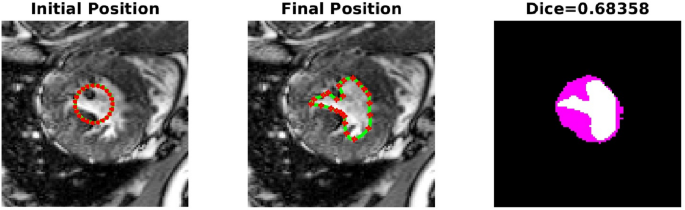

-

TC-2A,TC-2B: In the second case, Figs. 4 and 5 demonstrate the effect of integrating a convexity-preserving loss term in the segmentation of the left ventricle. As depicted in Fig. 4, a purely data-driven segmentation algorithm fails in cases where trabeculae and papillary muscles have comparable intensities to the myocardium. However, by incorporating prior shape information that preserves convexity, PICS is able to accurately segment the left ventricle even in the presence of confusing muscles, as shown in Fig. 5. The inclusion of the shape loss term results in an increase of the Dice score from 0.68 without the shape loss term to 0.92 with it. We also show the segmentation output with traditional Chan–Vese (https://scikit-image.org/docs/stable/auto_examples/segmentation/plot_chan_vese.html) and snake (https://scikit-image.org/docs/stable/auto_examples/edges/plot_active_contours.html) models in Fig. 6. In the level set formulation, the Chan–Vese model does not distinguish between the bright intensities of the left and right ventricle. On the other hand, the traditional snake model, even when initialized very close to the true mask, adheres to locations with sharp pixel gradients.